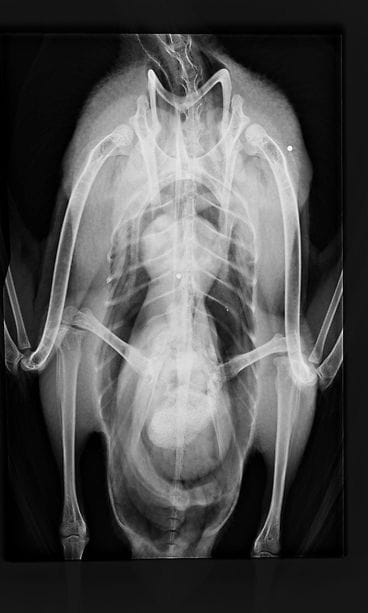

Helsingin pelastuslaitos toi Kuusisaaresta hoidettavaksi kanadanhanhen, jonka siivet oli väännetty kaksin kerroin ympäri.

– Pelastuslaitos toi sen saatteella, että linnulla on siivet solmussa. En silloin käsittänyt, että ne olivat konkreettisesti solmussa, Pulli kuvailee tilannetta MTV Uutiset Livessä.